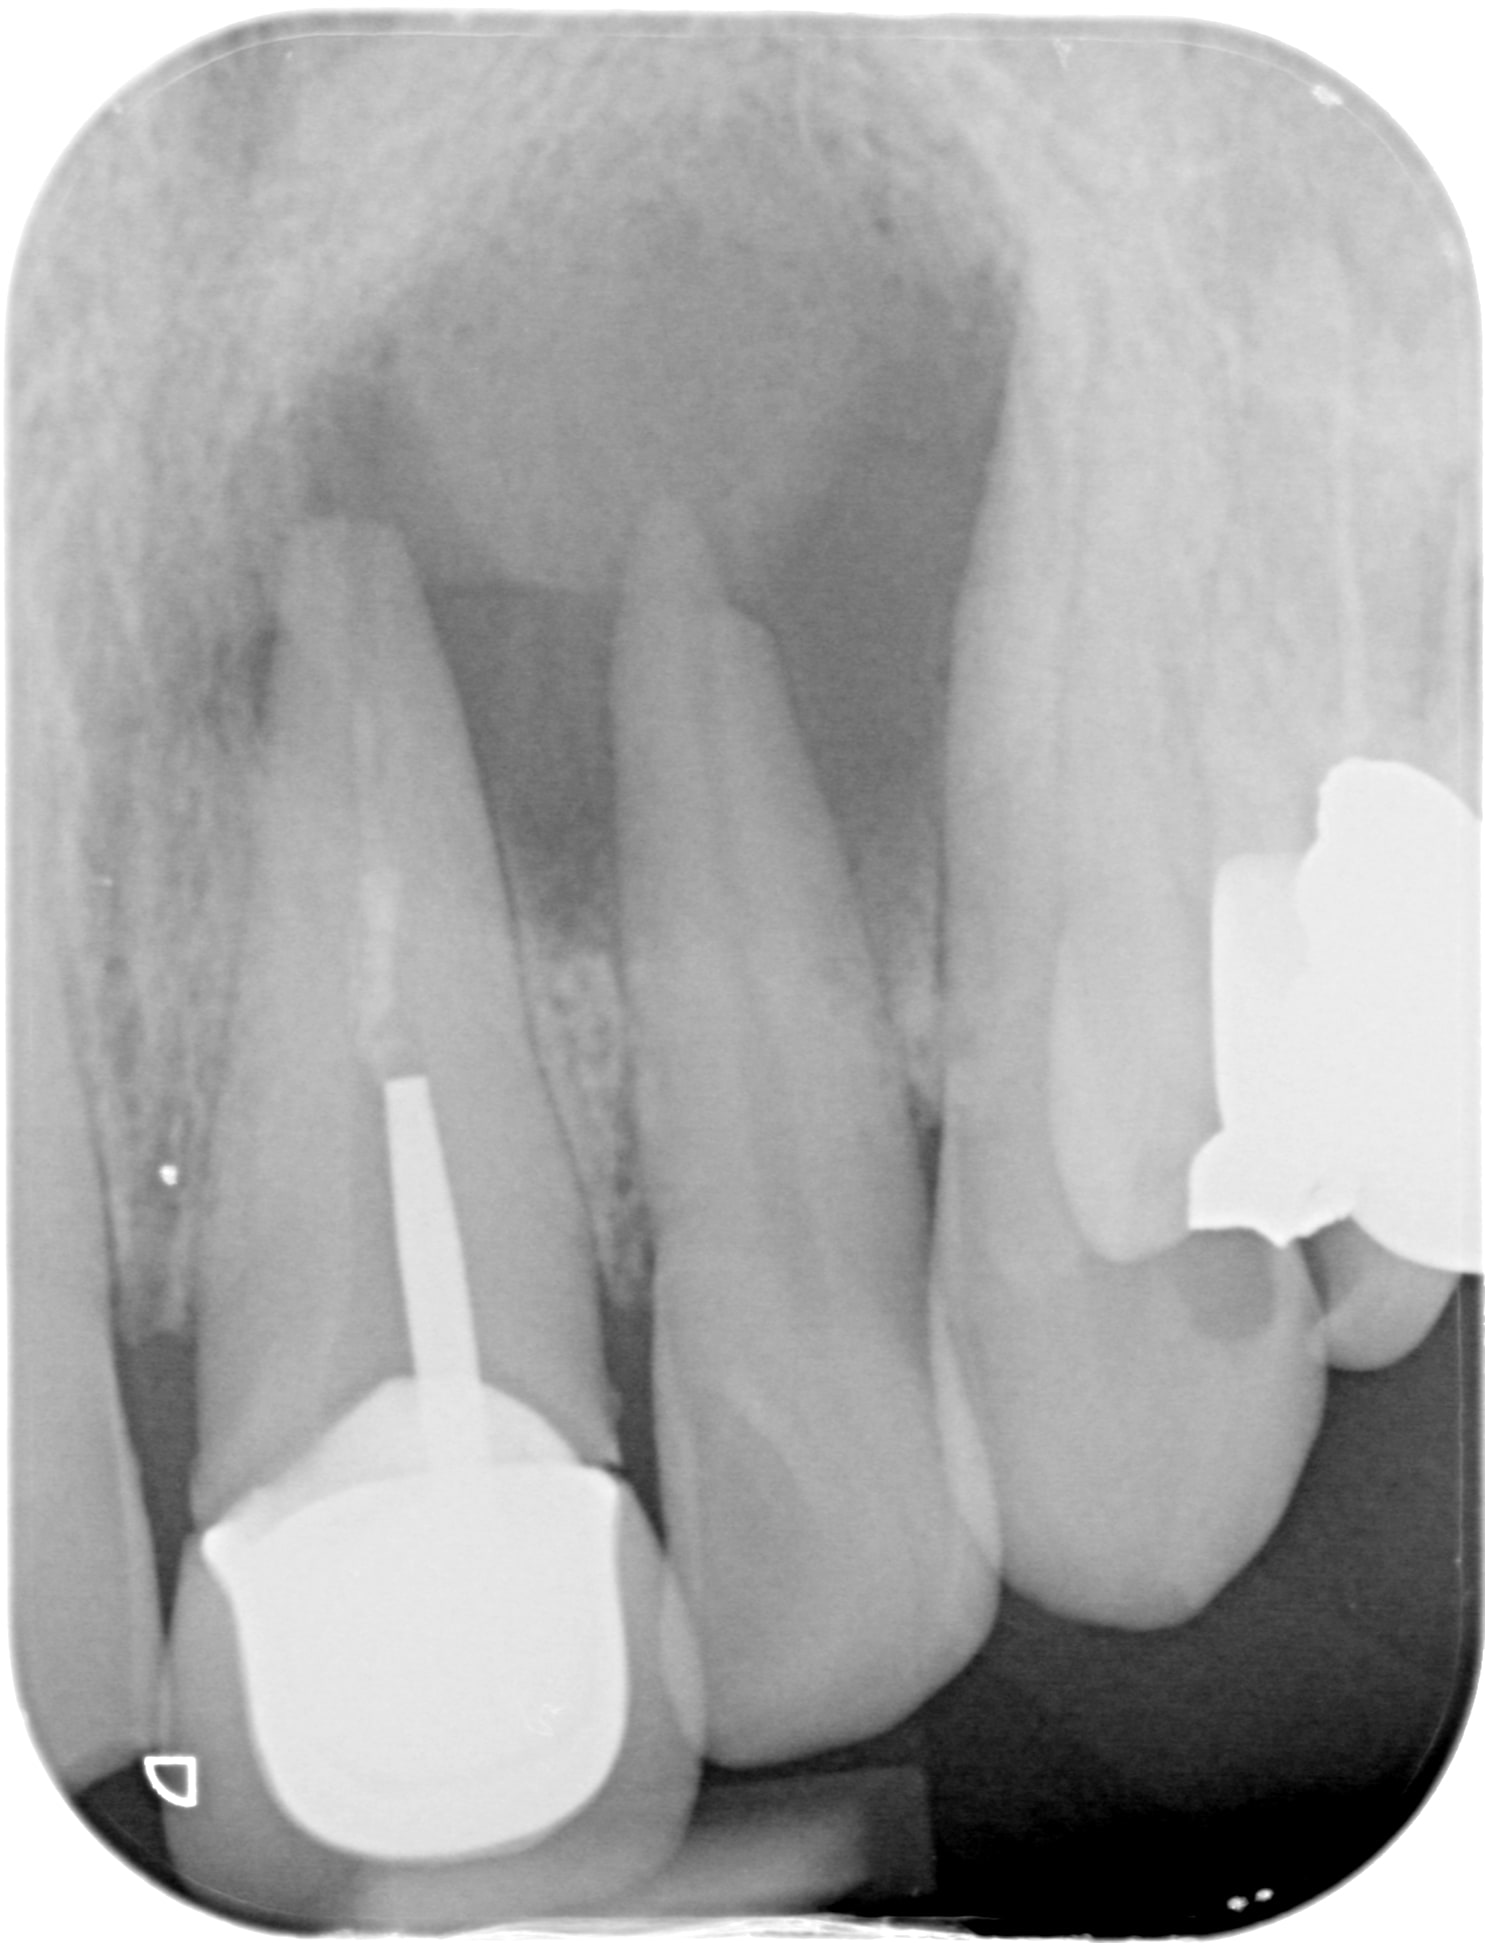

Img 2951 flo3gr - Eugenol